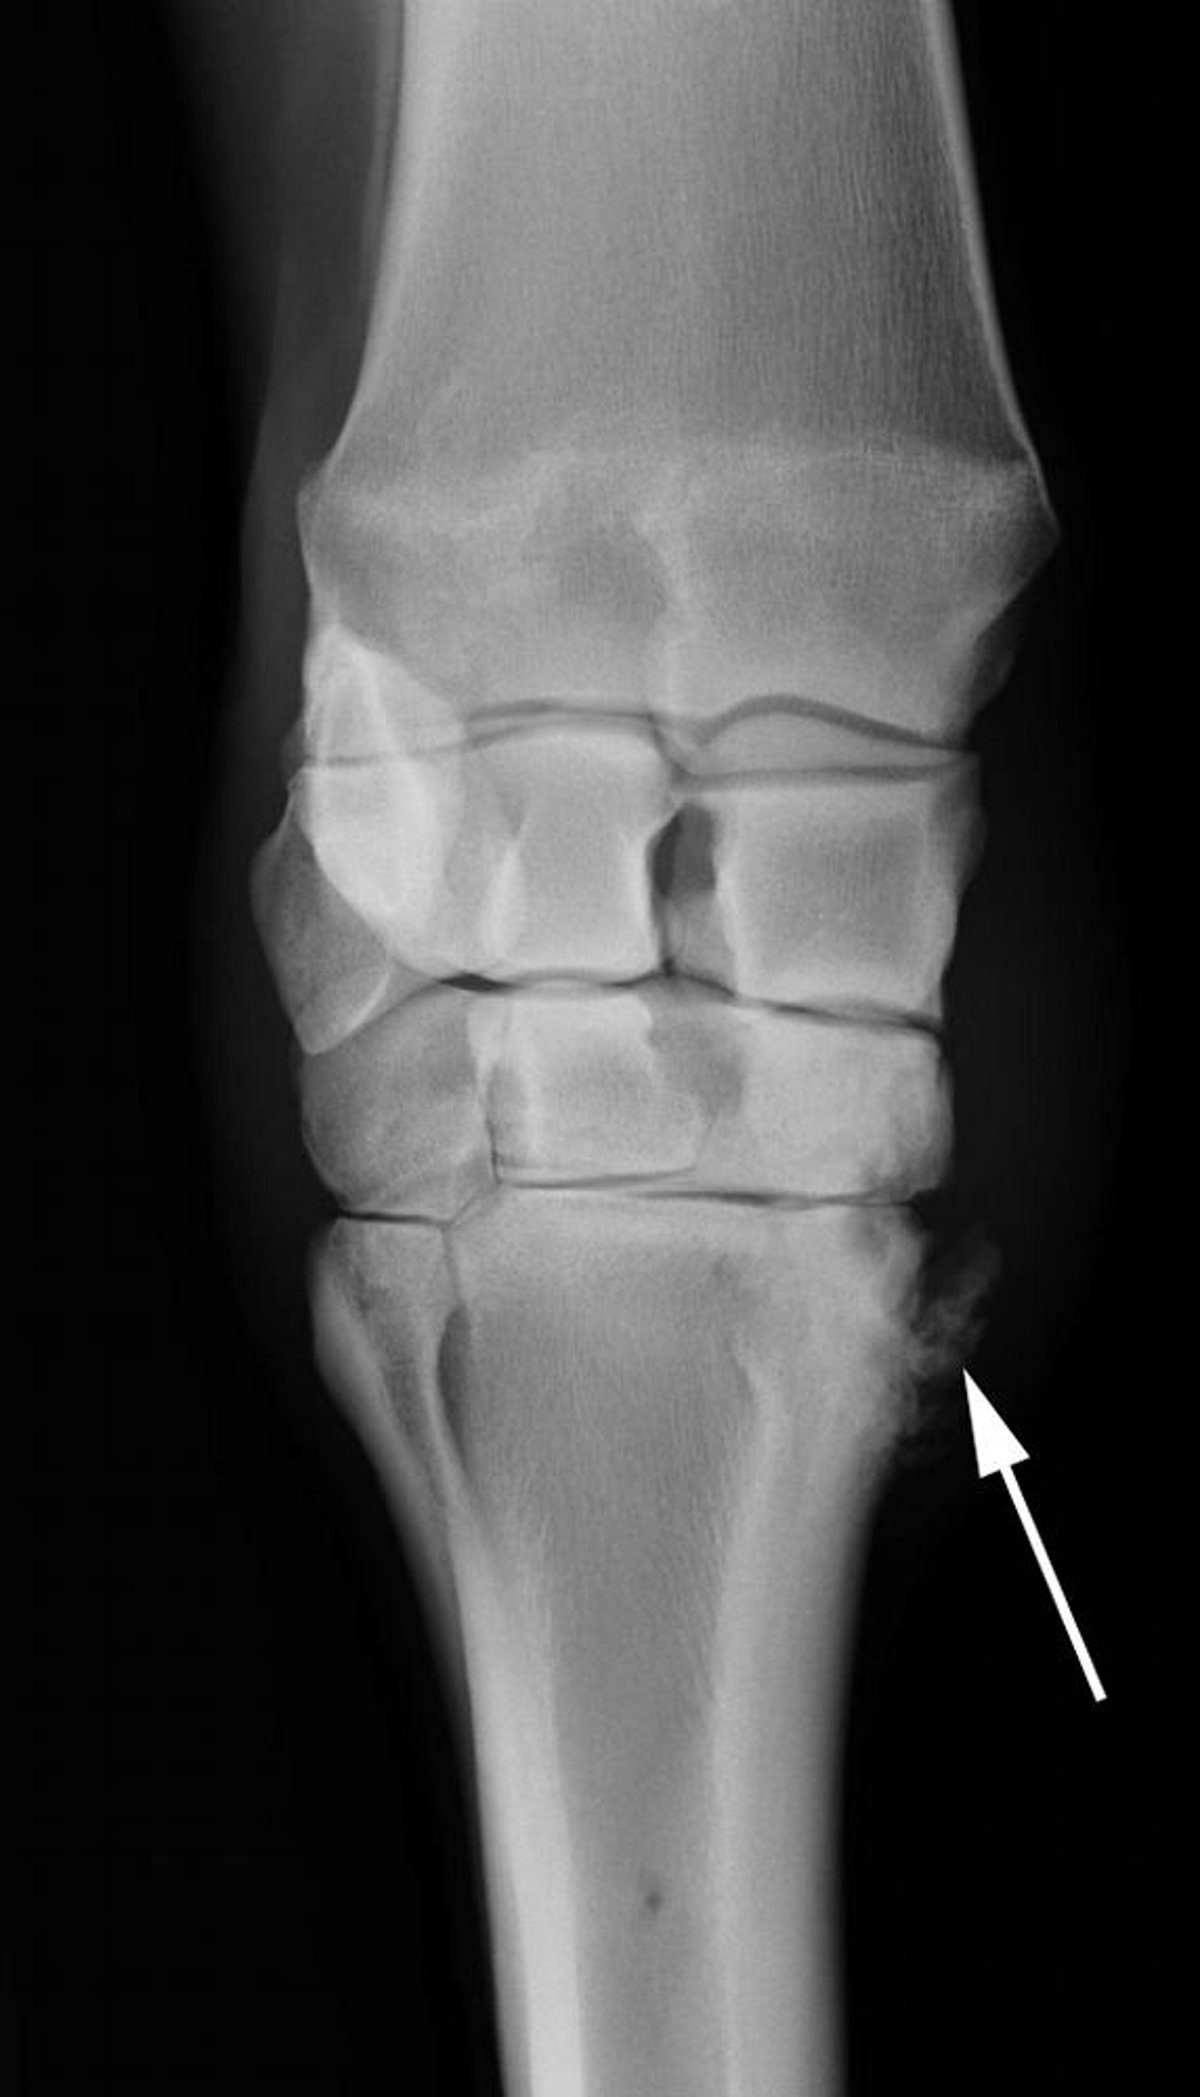

Osteoartritis de la articulación carpometacarpiana, radiografía, caballo

Proliferación notable de hueso nuevo (flecha) en un caballo con osteoartritis de la articulación carpometacarpiana.

Cortesía del Dr. Matthew T. Brokken.